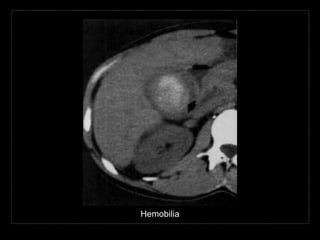

HEMOBILIA

Presencia de sangrado hacia el

árbol biliar y sangre en la bilis.

• Causas:

• trauma/biopsia

• enfermedad inflamatoria

• colelitiasis

• tumor

• anormalidades vasculares

Hallazgos por TC y RM

• contenido con densidad/intensidad hemática

• contenido heterogéneo de la vesícula biliar

• posición dependiente

• vesícula distendida con engrosamiento de su

pared

• + C

• reforzamiento de la pared vesicular